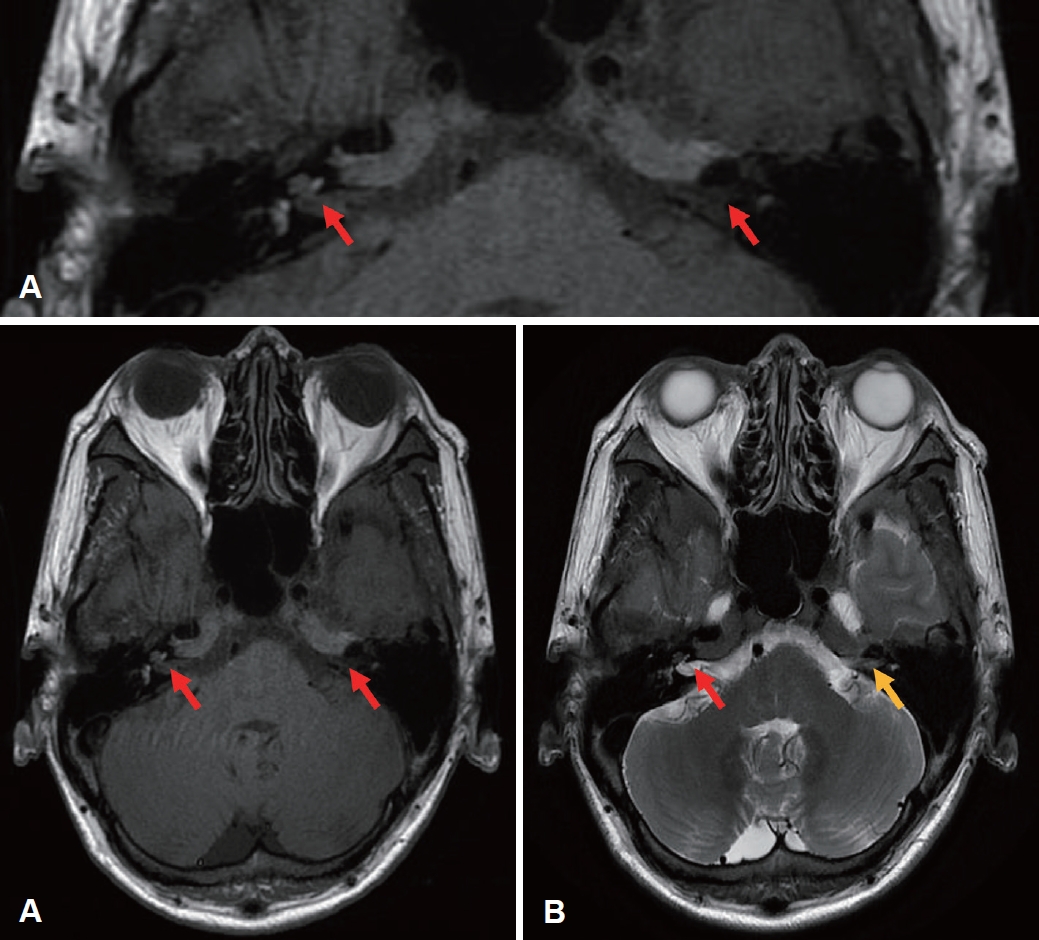

입원 후 시행한 혈액검사상 수두대상포진 바이러스 항체는 음성이었으며 C반응 단백질은 1.09 mg/dL로 약간 증가되어 있었고, 백혈구 699200/mm3, 적혈구 2280/mm3, 혈색소 9.6 g/dL, 헤마토크리트 23.9%, 혈소판 78000/mm3로 백혈구 수치가 현저히 상승했으며 적혈구, 혈색소, 헤마토크리트는 감소해 있었다. 측두골 단층촬영에서는 이상소견이 확인되지 않았으나 T1 강조 자기공명영상 촬영에서 양측 와우, 미로 내에서 고강도 신호, T2 강조 자기공명영상 촬영에서 좌측 와우, 미로 내 저강도 신호가 확인되어 inner ear hemorrhage 를 시사하는 소견이었다(Fig. 3).

NotesAuthor contributions Conceptualization: Da Jung Jung. Data curation: Jigon Son, Da Hyun Chung. Funding acquisition: Da Jung Jung. Investigation: Da Hyun Chung. Methodology: Jigon Son, JI HYUN SONG. Project administration: Da Jung Jung. Resources: JI HYUN SONG. Supervision: Da Jung Jung. Validation: Da Hyun Chung. Visualization: Jigon Son. Writing—original draft: Jigon Son. Writing—review & editing: Da Jung Jung. Fig. 2.A case of 48-year-old male who visited our clinic with bilateral hearing loss. A: The air conduction threshold defined as the weighted four-frequency pure tone average was 120 dB in the right ear and 51 dB in the left ear on admission. B: There was no analyzable wave response in auditory brainstem response exam on second day of hospitalization. Fig. 3.MR images. A: Axial image of T1-weighted MR using contrast shows high signal intensity of both cochlear and semicircular canals (red arrow). B: Axial image of T2-weighted MR using contrast shows decreased signal intensity of left cochlear or labyrinth (yellow arrow). Table 1.Clinicopathological characteristics of CML patients presenting hearing impairment